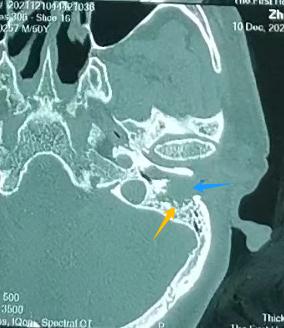

左耳:外耳道有肿物(左图)

对比右耳:外耳道通畅,鼓膜完整(右图)

张宏征发现,周先生左外耳道长了淡红色肿物,结合他长期的掏耳习惯,怀疑很可能是外耳道癌,立即为他进行外耳道肿物病理检查,结果证实周先生患的是罕见的“左外耳道鳞状细胞癌”。